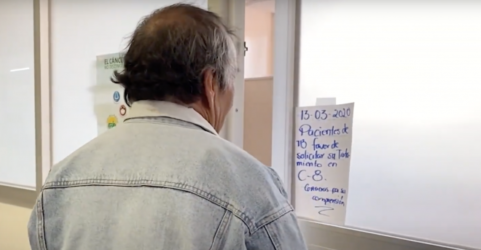

Agregó que, los medicamentos pueden causar reacciones adversas. En ese entonces, la Secretaría de Salud no colaboro de manera plena ante la situación, así que recurrieron a La Comisión Mexicana de Defensa y Promoción de los Derechos Humanos, A.C. (CMDPDH) junto a la Defensoría de Salud, el caso fue llevado a la Comisión Interamericana de Derechos Humanos (CIDH) logrando medidas cautelares a estas personas.